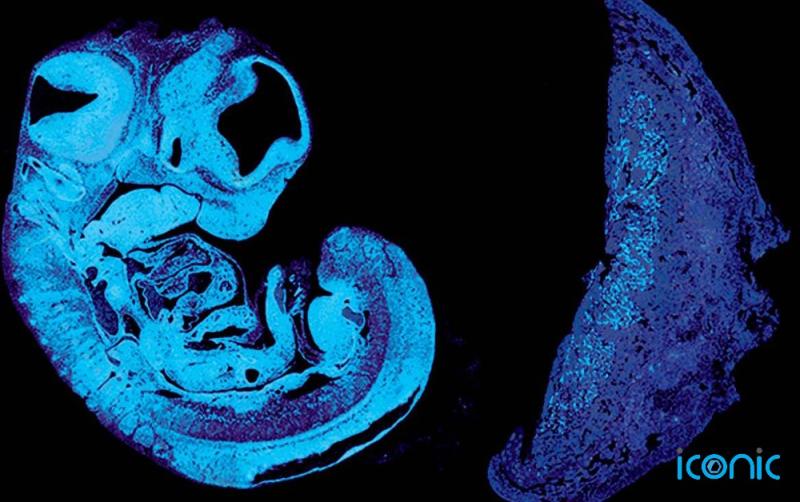

In a study of genetically-engineered embryonic mice, published today in Developmental Cell, the scientists found that the foetus produces the signal, known as IGF2, to encourage the growth of blood vessels in the placenta, and that this involves a “tug of war” between genes inherited from the mother and father.

The response of blood vessels in the placenta to IGF2 in mice is mediated by the protein IGF2R. Genes that produce IGF2 and IGF2R are “imprinted”, with molecular switches that identify their parental origin, and these can switch them on or off.

Only the copy of IGF2 inherited from the father is active, while only the copy of IGF2R inherited from the mother is active.